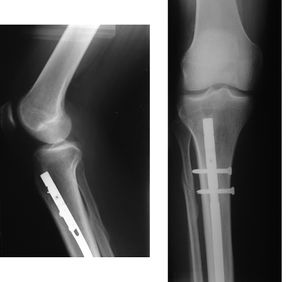

منظر داخلي وخارجي لذراع به كسر مركب. كلا منهما قبل وبعد الجراحة. | |

- كسر مركب: وفيه تنكسر العظمة ويتمزق الجلد الذي فوقها.